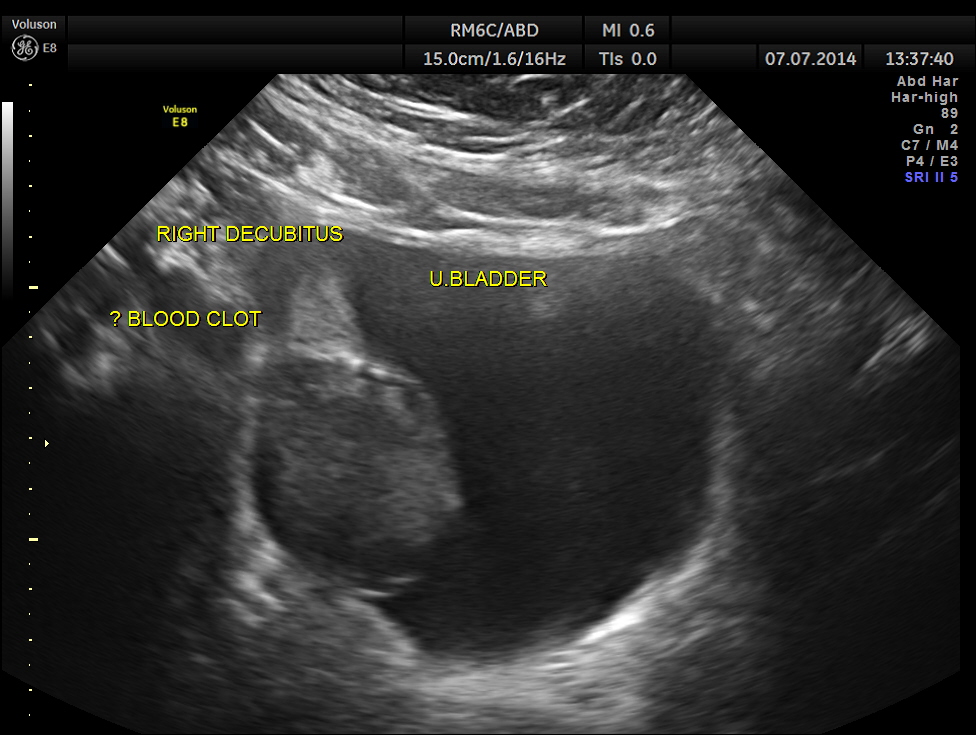

The urinary bladder showed ? mass lesion at first look.

With change of position this ” mass ” was seen to roll within the urinary bladder , suggestive of blood clot.

In this patient the increased vascularity is brought out very well by glass body imaging . Clots of blood seen in the urinary bladder gave the false impression of a mass lesion in the bladder initially.The importance of a dynamic study of turning the patient to the sides should always be remembered.